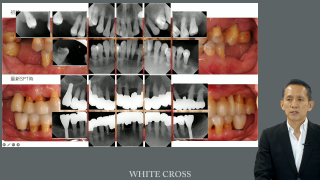

“歯周病はなったら治らない”ちまたでよく耳にします。歯周病って原因不明の不治の病なのでしょうか?歯周病は治らないと言っている歯科医師でも歯周病の原因に関しては、歯周病原性細菌と言う人が多くいらっしゃいます。歯周病に限らず、原因と疾患の因果関係がはっきりしている病気の治療は非常にシンプルです。やるべきことはただ一つ、原因の除去です。歯周病原性細菌は口腔内でプラーク/バイオフィルムに姿を変えて存在しているので、「歯垢を除去する」、これを確実に行うことこそが歯周治療を成功に導く鍵となります。

今回は「歯周病はなおる」をキーワードに、歯周病を掘り下げたいと思います。

そして今回のもう一つのトピックであるインプラント周囲疾患です。インプラント治療をしていない診療室に勤務している衛生士の皆さんや歯科医師の先生方にとって、インプラント周囲疾患治療は、とっつきにくい分野でしょう。でも、歯周治療をしていない歯科医院は少数派ではないでしょうか。そこで、多くの共通の臨床症状を呈するインプラント周囲疾患と歯周疾患を、歯周病と対比することで理解し、するしないは別としてインプラント周囲疾患に立ち向かうための基本的な知識の習得を目指しました。